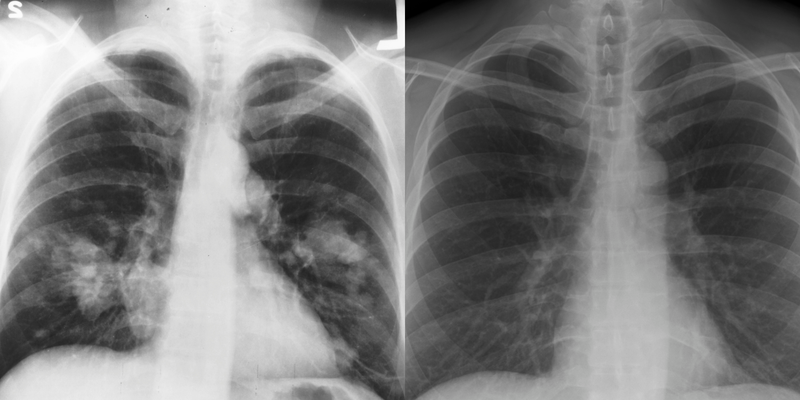

“Phổi trắng” là cách gọi mô tả hình ảnh bất thường của phổi trên phim chụp X-quang hoặc CT ngực. Ở người khỏe mạnh, phổi chứa nhiều không khí nên hình ảnh thường khá trong, cho phép tia X đi qua dễ dàng. Ngược lại, khi mô phổi bị tổn thương như viêm nhiễm, tích tụ dịch, xơ hóa hoặc xuất hiện khối u, mật độ mô tăng lên làm vùng phổi hiện lên mờ trắng trên phim.

Hình ảnh phổi trắng khi chụp X-quang